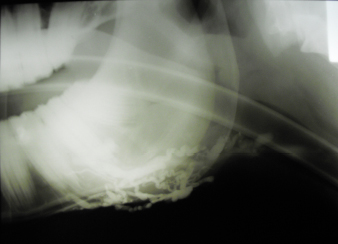

The left jugular vein appeared as an anechoic tubular structure which collapsed under the probe pressure, the color Doppler examination revealed normal blood flow within the vessel (Fig. 3). Bi-dimensional ultrasonography of the right jugular vein showed a heterogeneous, non-cavitating, hypoechoic structure occluding a narrowed right jugular vein for about 30 cm of length localized in the proximal and mid-portion of the neck compatible with a thrombus (Fig. 4). The color Doppler examination showed blood flow through the lateral portions of the thrombus in the cranial and mid-portions of the right jugular vein (Fig. 5). Cranially to the thrombus, a marked distension of the maxillary and linguofacial veins was evident, with a turbulent and echogenic flow; the latter was compatible with blood stasis near the thrombus (Fig. 6). Caudally to the thrombus, the right jugular vein presented reduced diameter, thickened walls, and normal blood flow (Fig. 7). The cranial part of the thrombus originated from a heterogeneous scare tissue, localized at the level of the right mandibular angle (Fig. 8). After injection of the first saline contrast bolus in a right facial vein, no microbubbles appeared in the right jugular vein, caudally to the thrombus, proving the presence of a complete right jugular vein occlusion. On the contrary, after injection of the second bolus, microbubbles were visualized in the left jugular vein as small, intense, echo signals within the vein lumen, demonstrating the presence of collateral circulation that drained the blood from the right facial veins to the left jugular vein (Fig. 9). Venography results confirmed the complete occlusion of the right jugular vein and the presence of submandibular venous collaterals that connected the right facial veins with the left jugular vein (Figs. 10 and 11). Based on the previous results, the diagnosis of JVT with complete occlusion of the vessel lumen was confirmed. The horse’s owner refused any proposed medical or surgical therapy.

Fig. 10. Venographic examination, latero-lateral view. Note the large number of collateral vessels draining the contrast.

Fig. 11. Venographic examination, ventro-dorsal view. Note the large number of collateral vessels draining the contrast.